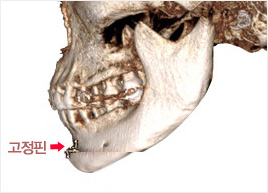

턱 끝 신경선을 피해서 턱 끝 뼈를 절골

합니다.

Check 02

Check 02

절골한 턱 끝을 수술 계획에 따라 앞으로

이동시킵니다.

Check 03

Check 03

절골한 턱 끝을 고정핀으로 고정시켜 주고

봉합합니다.